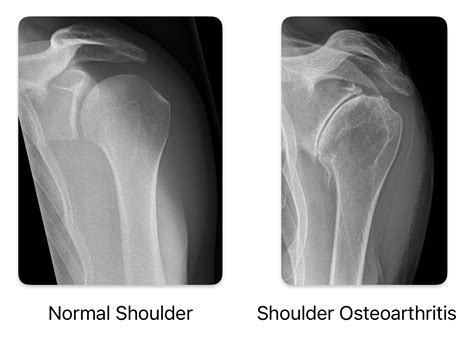

The shoulder joint is composed of the humeral head (the ball) and the glenoid (the socket). When the smooth cartilage that cushions these bones wears away, the bones begin to rub against each other, causing the inflammation and stiffness we recognize as arthritis. While age is the most common factor for osteoarthritis, other conditions like rheumatoid arthritis involve the body’s immune system attacking the joint lining. Regardless of the type, seeking early Arthritis In Shoulder Treatments is essential to prevent further degradation of the joint structure.